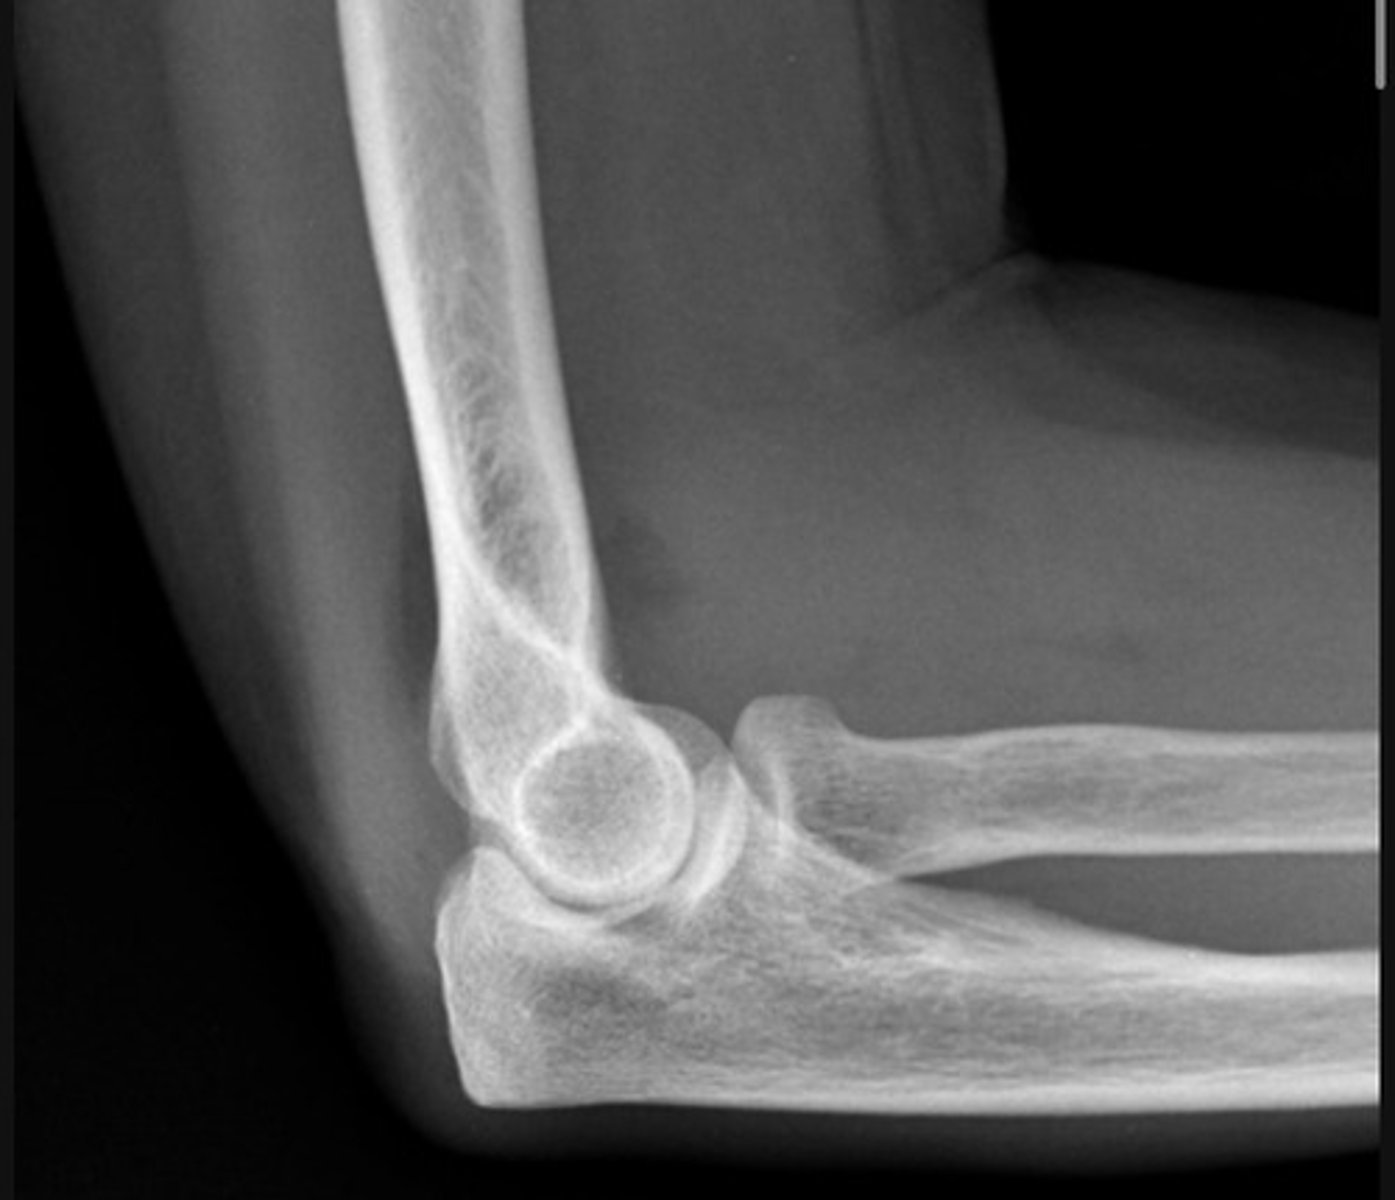

Likely a radial head fracture (adult)

Monteggia fracture-dislocation - Lateral

a fracture of the ulnar shaft with dislocation of the radial head at the elbow

The radiocapitellar line should pass through the middle of the capitulum of the humerus